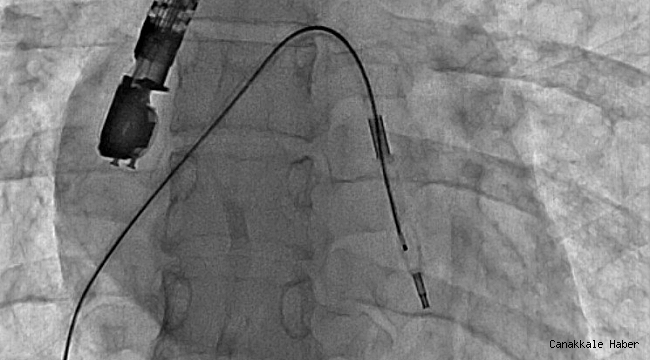

Mitral balon operasyonu adım adım kaydedildi

Eskişehir Şehir Hastanesi'nde ilk defa mitral balon operasyonu yapıldı. Operasyon, anjiyografi cihazı ile adım adım kaydedildi.Eskişehir Şehir Hastanesi'nde Kardiyoloji Uzmanı Dr....

Eskişehir Şehir Hastanesi'nde Kardiyoloji Uzmanı Dr. Mehmet Özgeyik ve 4 kişilik ekibi tarafından ilk defa mitral balon operasyonu yapıldı. Türkiye'de az sayıda yapılan kalp kapağı balon işlemiyle yeni anne olmuş genç bir hasta sağlığına kavuştu. Bu sayede hastalar ameliyat olmaktan, ömür boyu kan sulandırıcı ilaçlar kullanmaktan ve metal bir kalp kapağı ile yaşamaktan kurtuluyor.

Gerçekleşen başarılı operasyon hakkında konuşan Kardiyoloji Uzmanı Dr. Mehmet Özgeyik, "Bu işlemi genellikle kalp kapaklarında ciddi darlık olan genç hastaların kişilere uyguluyoruz. Buradaki amacımız ameliyat olmadan, kasıktan küçük iki damar yolu açarak hastalarımızın kapak darlıklarını uzun süreli olarak genişletmeyi hedefliyoruz. Burada 23 yaşında yeni anne olmuş genç bir hastamıza müdahale yaptık. Hastamız ya kapak ameliyatı olacaktı ya da bu işlem sayesinde kapak darlığını aşmayı planlıyorduk. İşlem gayet başarılı oldu. Hastamızın kapak darlığını genişlettik. En azından 10-15 sene boyunca ameliyata gerek kalmadan hastamızı ilaç tedavisiyle takip etmeyi planlıyoruz" diye konuştu.

Cerrahi operasyonlar yerine mitral balon işlemiyle hastaları sağlıklarına kavuşturmak istediklerini aktaran Dr. Özgeyik, "Hastanemizde ilk kez yapılan bir işlem. Bu işlem için uygun hasta bulmak biraz zor oluyor çünkü çok sık yapılan bir işlem değil. Fakat gelecekte hasta portföyümüzün de artması ile birlikte daha sık yapmayı planlıyoruz. En azından hastalarımızı büyük bir cerrahi operasyona vermeden böyle küçük işlemlerle hayat kalitelerini artırmayı planlıyoruz. Hastamız ameliyata gitmiş olsaydı büyük bir operasyon geçirmiş olacaktı. Göğüs bölgesinde büyük bir kesiğe maruz kalacaktı. Aynı zamanda ömür boyu kullanması gereken farklı ilaçlar olacaktı. Hasta kendisine ait olmayan metal bir kapakla yaşamak zorunda kalacaktı. Biz bu işlemde hastaya kasıktan iki tane damar yolu açtık. Hastaya neşter ile kesme işlemi uygulamaktan kurtardık. Ayrıca hastanın hayatı boyunca kullanacağı kan sulandırıcı ilaçları uzunca bir süre ertelemiş olduk. En önemlisi de hastanın kendi kalp kapağını kullanmasını sağlamış olduk ve metal kapak yükünden kurtulmuş oldu" şeklinde konuştu.